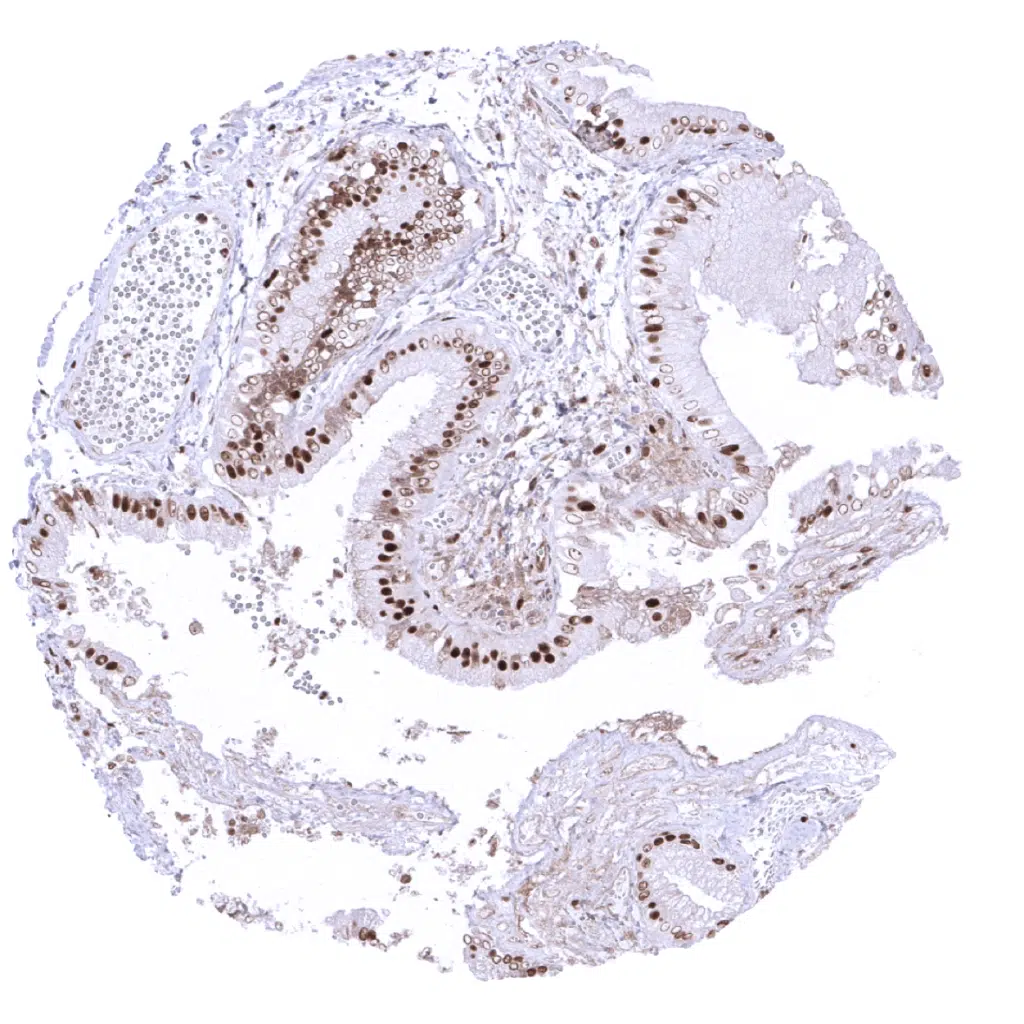

Duodenum, Brunner gland